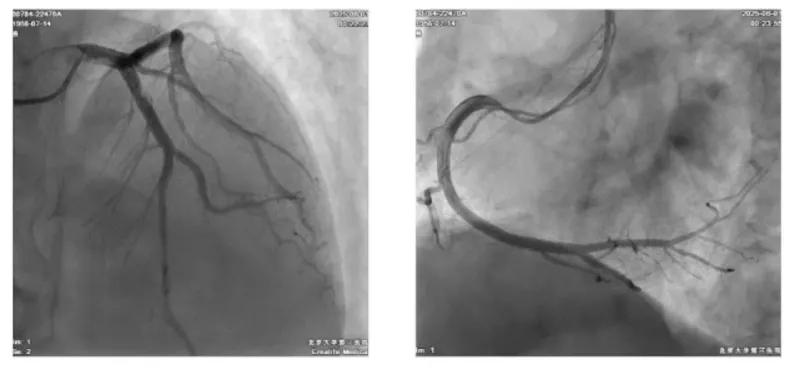

患者66岁老年男性,急性病程胸痛5个小时入院就诊。考虑到患者年龄、性别,及其高血压、高脂血症、吸烟、饮酒等心血管危险因素,首先怀疑急性冠脉综合征可能,行冠脉造影排除大血管狭窄后,行腺苷负荷超声心动图检查。患者CFR值1.88,确诊为冠状动脉微循环障碍(CMVD),初步考虑患者胸痛症状与CMVD相关。